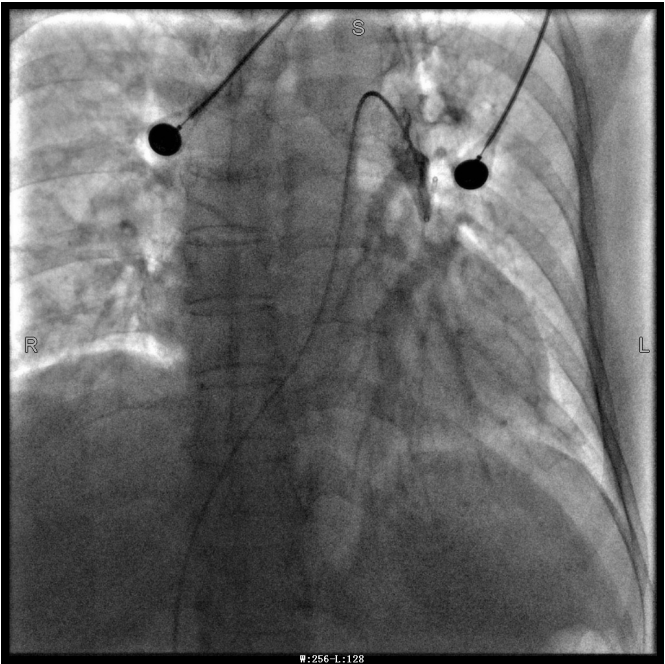

譚婆婆今年已經72歲了,因“突發意識障礙2次”到璧山區人民醫院神經內科治療。譚婆婆沒有基礎心臟病病史,但近段時間活動耐量明顯下降,稍做活動就出現呼吸困難。入院后查BNP及心臟彩超均未提示明顯異常,查D二聚體明顯升高,經心血管內科周波醫師會診后轉入科室繼續治療。在心血管內科主任、內科學(心血管病)博士于長青的指導下,周波醫師成功完成醫院首例“一站式”微創介入手術。在影像中,可以清晰地看到堵塞的血管經溶栓治療后,重新暢通無阻,流動起支撐生命的血液。

肺動脈導管局部置管溶栓術是通過肺動脈造影確定堵塞的肺動脈部位,然后導管尖端置于血栓處,將尿激酶、鏈激酶或重組組織型纖維蛋白溶酶原激活劑直接注入血栓處,新鮮血栓在足量的溶栓劑作用下溶解。肺動脈內局部用藥特別是小劑量時可減少出血并發癥。

第三章未標注圖像為術后圖像